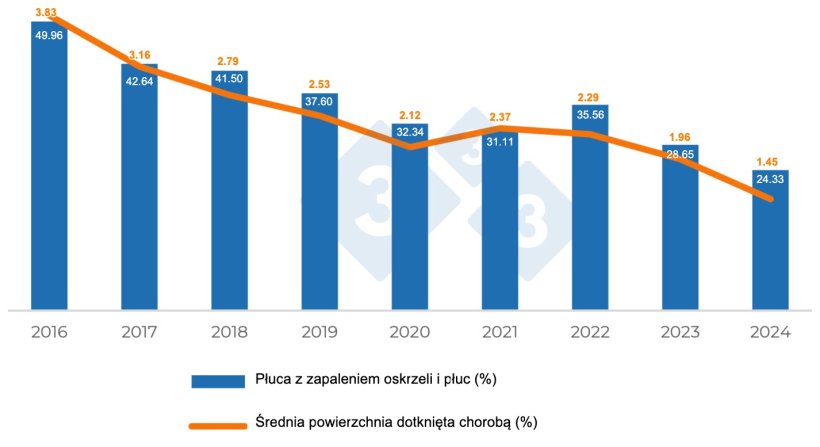

W Hiszpanii, po przeanalizowaniu ponad 6500 partii świń i ponad miliona płuc, zaobserwowaliśmy zmniejszenie stopnia występowania zmian chorobowych zgodnych z Mycoplasma hyopneumoniae od 2016 r. do chwili obecnej (tabela 1 i wykres 1), zarówno w:

- częstość występowania zmian w płucach (spadek z 49,96% do 23,71%)

- średnia powierzchnia płuc dotkniętych zmianami (spadek z 3,83% do 1,39%)

Tabela 1. Ewolucja zmian w płucach w latach 2016–2024 w Hiszpanii.

| 2016 | 2017 | 2018 | 2019 | 2020 | 2021 | 2022 | 2023 | 2024 |

|---|---|---|---|---|---|---|---|---|

| Liczba przebadanych płuc | ||||||||

| 76,868 | 154,817 | 214,702 | 184,741 | 100,017 | 109,251 | 68,786 | 93,568 | 173,220 |

| % Płuca z zapaleniem oskrzeli i płuc | ||||||||

| 49.96 | 42.64 | 41.50 | 37.60 | 32.34 | 31.11 | 35.56 | 28.65 | 24.33 |

| % Średnia powierzchnia płuc dotknięta chorobą | ||||||||

| 3.83 | 3.16 | 2.79 | 2.53 | 2.12 | 2.37 | 2.29 | 1.96 | 1.45 |

Wykres 1. Ewolucja zmian chorobowych zgodnych z Mycoplasma hyopneumoniae.

W latach 2021 i 2022 zaobserwowaliśmy niewielki wzrost, prawdopodobnie spowodowany współzakażeniami wysoce zjadliwymi szczepami PRRS, które doprowadziły do nasilenia obserwowanych zmian chorobowych i ogólnego pogorszenia stanu zdrowia zwierząt w niektórych obszarach.

Ta poprawa obserwowana na przestrzeni lat może wynikać zarówno z lepszych strategii zwalczania problemów spowodowanych przez Mycoplasma hyopneumoniae, jak i ze wzrostu masy ubojowej, a tym samym wieku zwierząt. W pewnym stopniu widać to w fakcie, że występowanie blizn nie zmniejsza się w takim samym tempie jak częstość występowania zmian chorobowych, ale raczej wydaje się pozostawać na stałym poziomie lub nawet wzrastać. Możliwe więc, że wiele zmian chorobowych zagoiło się i dlatego podczas uboju nie są one obserwowane jako zmiany zapalenia oskrzeli i płuc, ale jako blizny.